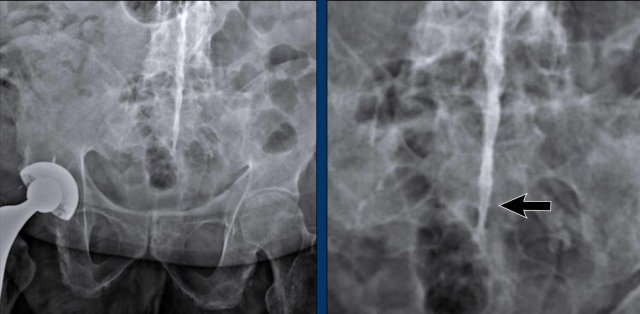

Ankylosing spondylitis Ankylosing spondylitis

Syndesmophytes

These images show syndesmophytes in the lumbar spine and ossification of the paraspinal ligaments.

When these syndesmophytes fuse, this produces the typical “bamboo spine” appearance.

Also note the ossification of the intervertebral disc and ankylosis of the facet joints.

Syndesmophytes have a typically vertical orientation.

Bridging and fusing is quite common.

As a result the spine looses its flexibility and can easily fracture even after a minor trauma.

Bamboo spine

Bamboo spine in ankylosing spondylitis.

Fusion of the lumbar spine by syndesmophytes and ossification of the paraspinal ligaments.

Notice the ligamentous calcification (arrow).

A rigid bamboo spine is prone to hyperextension fractures, even after mild trauma.

Always have a high suspicion of these fractures in a rigid spine!

Ankylosing spondylitis of the cervical spine Ankylosing spondylitis of the cervical spine

A bamboo spine often begins at the lumbar level and can ascend up to the cervical spine.

Notice the squaring of the vertebral bodies (arrow).

Dagger sign

The radiopaque central line on frontal radiographs of the spine due to ossification of the interspinous ligaments, known as the “dagger sign”, is a radiographic feature of ankylosing spondylitis.

Also note the complete fusion of the SI-joints.